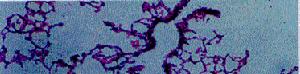

不動纖毛綜合徵本病為常染色體隱性遺傳現已證實纖毛軸絲含有100多種多肽任何1種多肽有缺陷,均可造成同樣的病理結果。因此具有明顯的遺傳異質性。有纖毛蛋白臂部分或完全缺失(單純外側或內側纖毛蛋白臂缺失、或雙側均缺失),有放射輻缺陷者,有中央鞘缺失。也有臨床症狀典型而纖毛超微結構正常者。其中以纖毛蛋白臂完全缺失者最為常見(占74%)。

ICS是一種和遺傳有關的纖毛結構缺陷。主要為纖毛蛋白臂或放射輻的缺陷,從而使纖毛運動異常,黏膜上纖毛清除功能障礙,以致造成反覆感染。